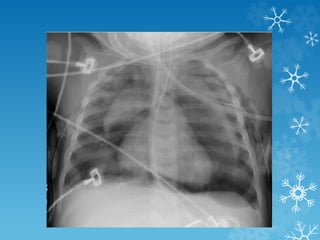

44 yrs. female – immunocompromised with altered mental status

44 yrs. female– immunocompromised with altered mental status